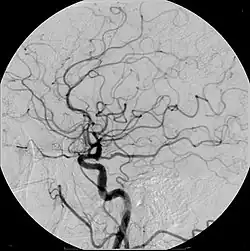

- Angiography (arterial investigations)

Iodinated contrast contains iodine. It is the main type of radiocontrast used for intravenous administration. Iodine has a particular advantage as a contrast agent for radiography because its innermost electron ("k-shell") binding energy is 33.2 keV, similar to the average energy of x-rays used in diagnostic radiography. When the incident x-ray energy is closer to the k-edge of the atom it encounters, photoelectric absorption is more likely to occur. Its uses include:

Organic iodine molecules used for contrast include iohexol, iodixanol and ioversol.